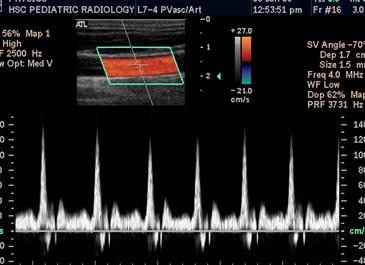

• Ультразвуковое дуплексное сканирование (УЗДС) — метод ультразвуковой диагностики, совмещающий в себе допплерографиию и В-метод. Последний помогает данному методу изучать не только кровоток, но и сами сосуды. Ток крови в сосудах изучается при помощи цветового картирования.

Современная методика позволяет использовать допплеровский эффект с цветной кодировкой.

Дуплексное сканирование проводится с помощью специального УЗИ-аппарата. Чувствительные датчики помещают на поверхность тела в районе исследуемых сосудистых сплетений. На монитор транслируется примерное изображение движения крови и тонуса стенок сосудов. Допплерография основывается на использовании допплеровского эффекта — свойства волн ультразвука отражаться в неизменном виде от движущихся предметов. Отличается только частота, зависящая от вектора движения датчика. Если он направлен в сторону органа, показатель увеличивается, и наоборот. Это позволяет исследовать кровоток при высокой скорости циркулирующей крови. Более усовершенствованные доплеровские методики используют кодирование цветом.

Ультразвуковое дуплексное сканирование — более сложная диагностическая методика, отличается сочетанием в себе В-режима и эффекта Доплера. Применение В-режима позволяет визуализировать исследуемые вены и артерии и изучить состояние окружающих тканей. Исследование тока крови в сосудах проводится с помощью цветового картирования доплер-методом или техники спектрального анализа.

В результате проведенного исследования и последующей компьютерной обработки данных можно получить показания, представленные в виде допплеровского спектра или цветовой картограммы кровотока. Картограмму получают, используя различные технологии цветового картирования и, по сути, она является «слепком» поперечного сечения исследуемого сосуда. Во время дуплексного обследования сосудов на экран монитора выводится изображение сосуда, что позволяет сделать визуальную оценку проходимости вены или артерии и найти причину, вызвавшую снижение скорости тока крови. С помощью УЗДС можно выявить такие патологические сосудистые состояния:

Исследования кровотока в сосудах осуществляется путём техники спектрального анализа или цветового допплеровского картирования. После компьютерной обработки полученных данных результат может быть представлен в виде цветовой картограммы кровотока или допплеровского спектра. С помощью различных технологий цветового картирования можно получить картограмму, которая напоминает поперечный разрез исследуемого органа. При дуплексном обследовании на экране появляется изображение сосуда, благодаря чему можно визуально оценить его проходимость и обнаружить причину, приведшую к уменьшению скорости кровотока.

Однако при допплерографии и дуплексном сканировании использование этого эффекта различно. При УЗДГ используется допплеровский режим, в результате которого врач на экране аппарата получает кривую, называемую допплеровский спектр. По этой кривой можно оценить функциональные показатели, характеризующие ток крови по сосуду, после чего делается вывод о наличии или отсутствии патологических изменений.

УЗДС отличается тем, что помимо допплера в нём используется В-режим. Последний даёт возможность получить на экране в реальном времени двухмерное изображение, благодаря чему врач видит структуру стенки сосуда, его проходимость, извитость, особенности хода. В этом методе может поочерёдно использоваться два вида допплеровского режима: с получением кривой и цветового картирования (ЦДК). В результате ЦДК на фоне двухмерного изображения появляется окрашивание тока крови в красный и синий цвет, который не зависит от вида сосуда. Прокрашивание его в разные цвета зависит от направления кровотока: если кровь движется по направлению к датчику, то просвет сосуда становится красным, в противном случае – синим.